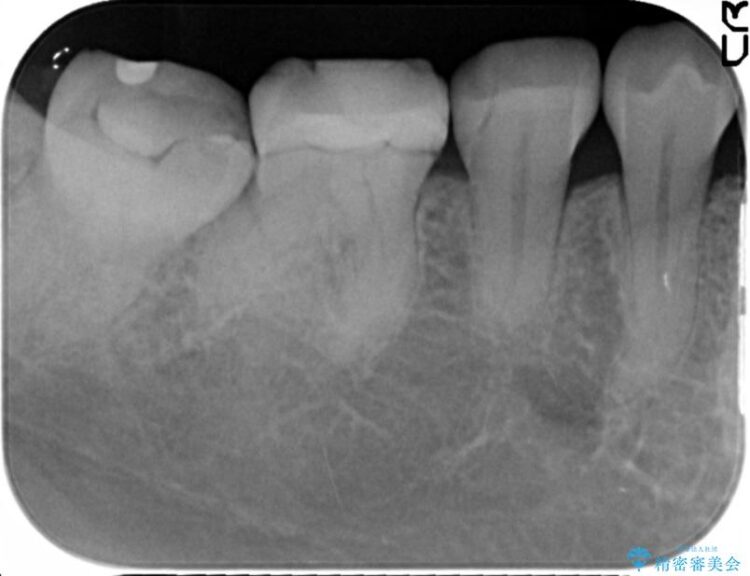

初診の際に撮影したレントゲンにて以前他院で治療していた詰め物が適合不良であることが判明し、再度治療をしてほしいとのご希望でした。

ぱっと見ただけでは特に問題ないように見えますが、レントゲンをよく確認すると詰め物と歯の間に隙間がはっきりと確認ができます。